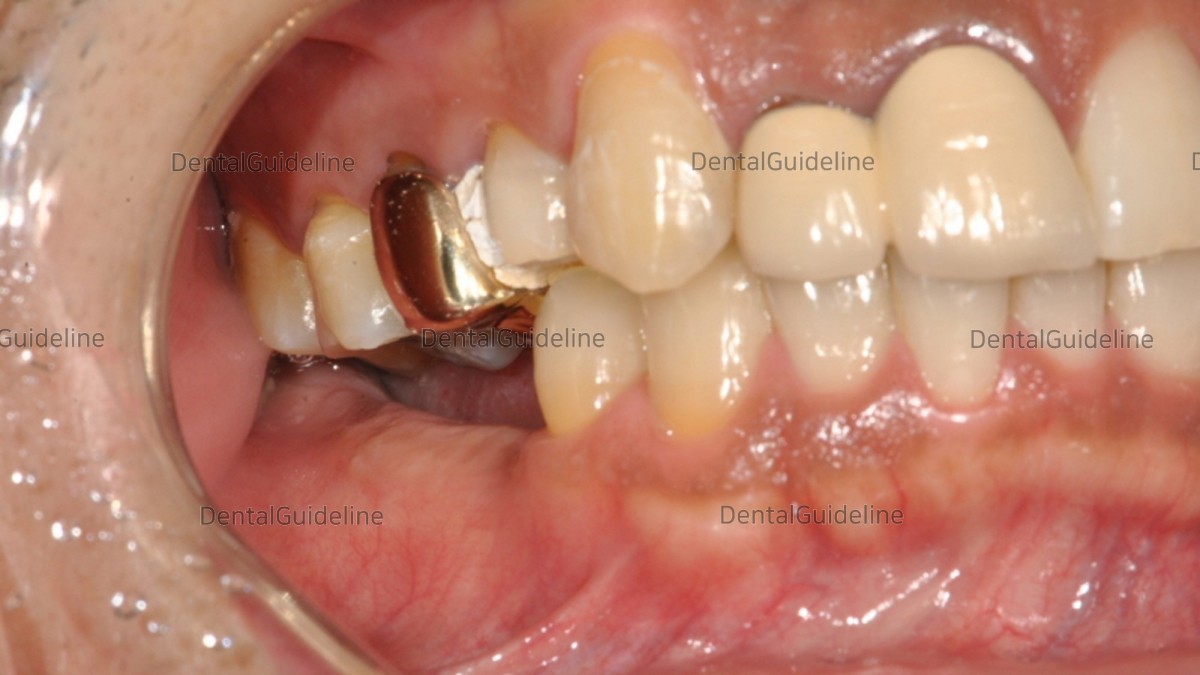

1. Initial photo. Due to the loss of the mandibular teeth for a long period, the maxillary teeth came down. For implant-supported restoration of the edentulous mandibular region, the occlusal elevation of the opposing maxillary teeth is necessary first.